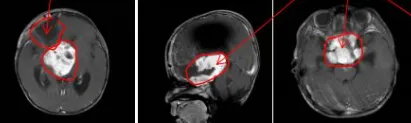

第一次术后

术中:联合手术成功近全切

为了保证孩子的安全和高切除率,巴教授教授与Concezio Di Rocco教授决定联合手术,通过额骨颅骨开颅术和大脑半球间穹窿入路肿瘤切除术直至Monro孔(室间孔),并沿着脑室壁向中脑行进。右侧视神经被肿瘤浸润包裹,但是左侧视神经被小心地从肿瘤肿块中剥离出来,垂体腺和垂体柄也被小心保护,无术中并发症。三脑室占位被全部切除,鞍上占位基本全部切除,视神经及周围血管被完整保护。